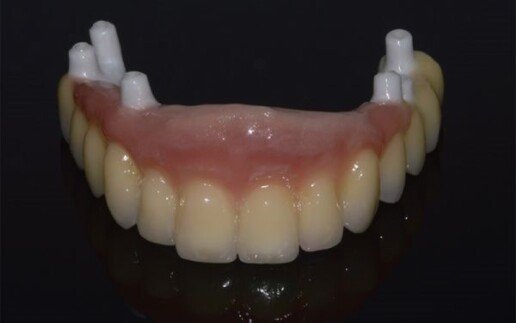

Riabilitazione totale superiore e inferiore su impianti. Gli esiti di una paradontite grave portano alla perdita totale dei denti. E’ necessario ricostruire sia i denti sia i tessuti molli e anche l’osso per il sostegno delle labbra.

In questo caso si è reso necessario il rialzo del seno mascellare bilaterale, per la ricostruzione dei tessuti duri (osso) e dei tessuti molli (gengiva). La paziente ha portato 25 anni una protesi incongrua, questo le ha provocato la perdita di tanto osso. Con la tecnologia CAD-CAM, è possibile ricostruire le protesi, partendo da un disegno al computer, e poi produrla attraverso una macchina che costruisce in 3D il pezzo in zirconio o altro materiale. Il tecnico di laboratorio provvede poi a personalizzare con la porcellana estetica.

Con la tecnologia CAD-CAM conoscendo già prima la posizione virtuale degli impianti, si può preparare il provvisorio che verrà applicato fisso lo stesso giorno della chirurgia.